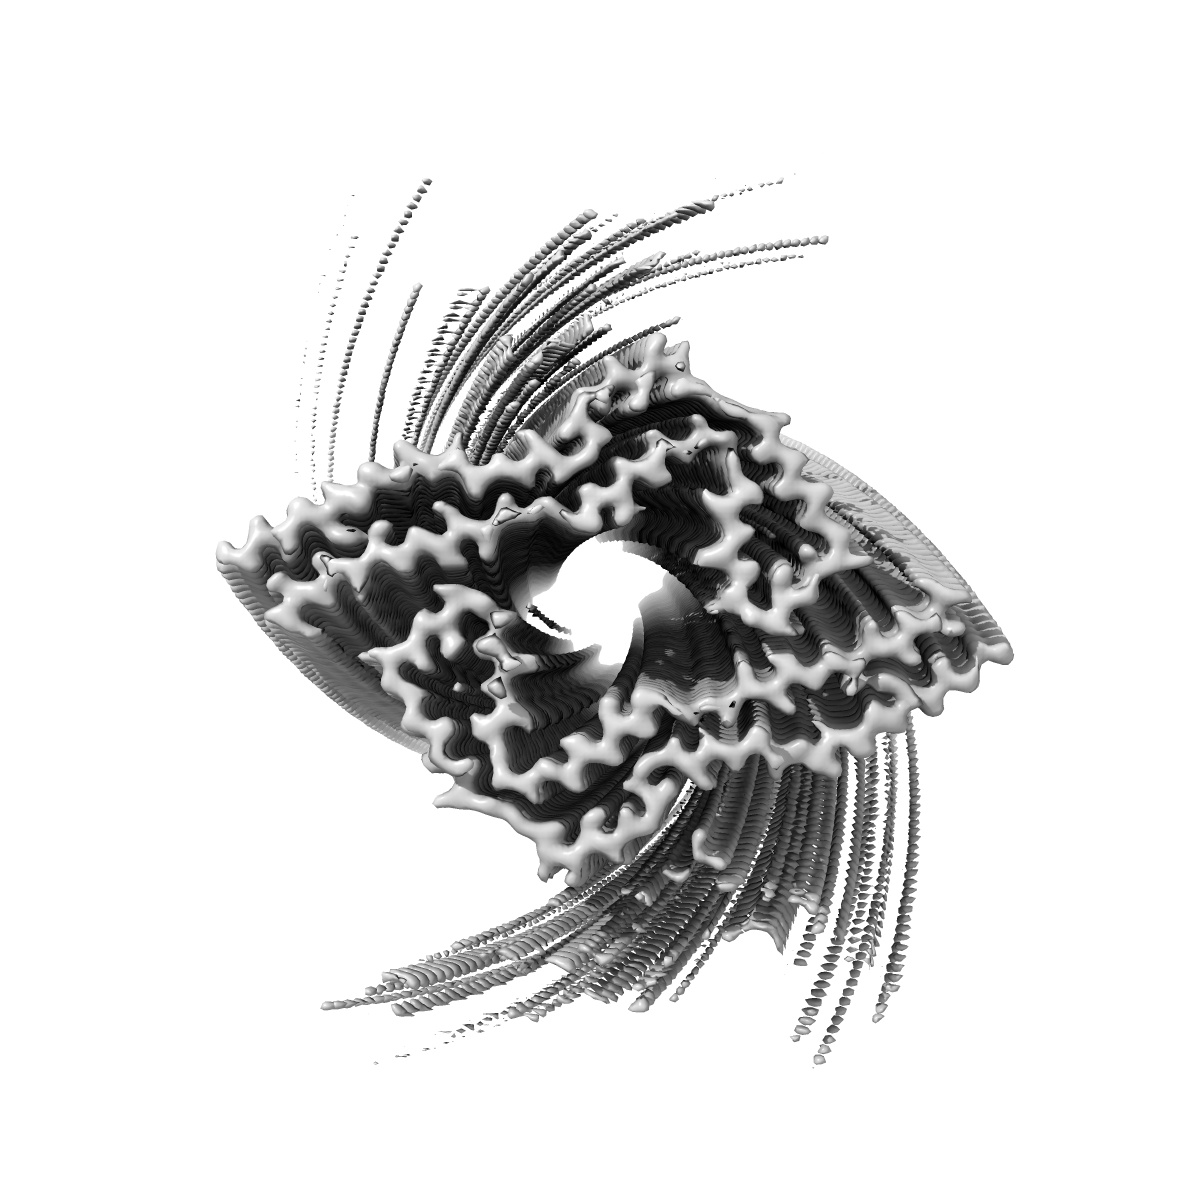

In vitro assembled 266/297 - 391 tau filaments with MgCl2 and NaCl (14b)

EMD-14044

Helical reconstruction

3.26 Å

Sample Organism: Homo sapiens

Sample: Tau

Fitted models: 7qkj

Deposition Authors: Lovestam S, Scheres SHW

Assembly of recombinant tau into filaments identical to those of Alzheimer's disease and chronic traumatic encephalopathy.

Lovestam S, Koh FA, van Knippenberg B , Kotecha A , Murzin AG, Goedert M , Scheres SHW

(2022) eLife , 11

PUBMED: 35244536

DOI: doi:10.7554/eLife.76494